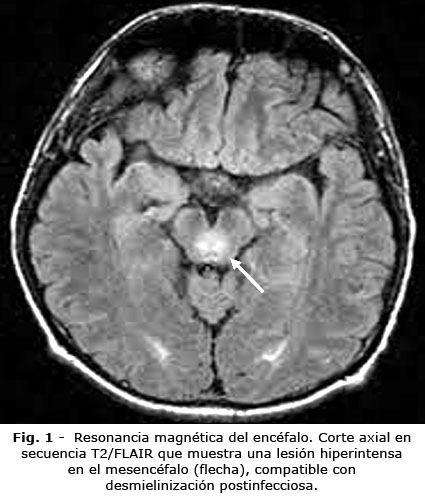

La resonancia magnética mostró lesiones hiperintensas en T2/FLAIR (Fig. 1) y en mesencéfalo y médula dorsal (D10) (Fig. 2), compatibles con desmielinización.

El cuadro clínico observado, se caracteriza por la tríada de afectación cerebelosa, piramidal y neuropsiquiátrica; reproduce el patrón descrito en el 78 % de los casos analizados por Zuhorn F y otros.(9) Desde la perspectiva imagenológica, las lesiones desmielinizantes en el mesencéfalo y la médula dorsal concuerdan con la localización típica reportada, en la cual, el 65 % de los casos muestra afectación predominante del tronco cerebral y la médula espinal.(10) Este patrón topográfico resulta clave para el diagnóstico diferencial con otras entidades, como la esclerosis múltiple y la neuromielitis óptica, que fueron descartadas en el paciente mediante criterios clínicos e imagenológicos establecidos.(11)

Las implicaciones clínicas de este caso son multifacéticas. Primero, refuerza la necesidad de la vigilancia neurológica prolongada, después de la COVID-19, independientemente de la gravedad inicial de la infección. Segundo, destaca el valor de la resonancia magnética como herramienta diagnóstica esencial en entornos con recursos limitados. Tercero, subraya la importancia de iniciar la terapia inmunomoduladora empírica, cuando la sospecha clínica sea elevada, particularmente si no se disponen de pruebas avanzadas para confirmar el diagnóstico.(18,19)